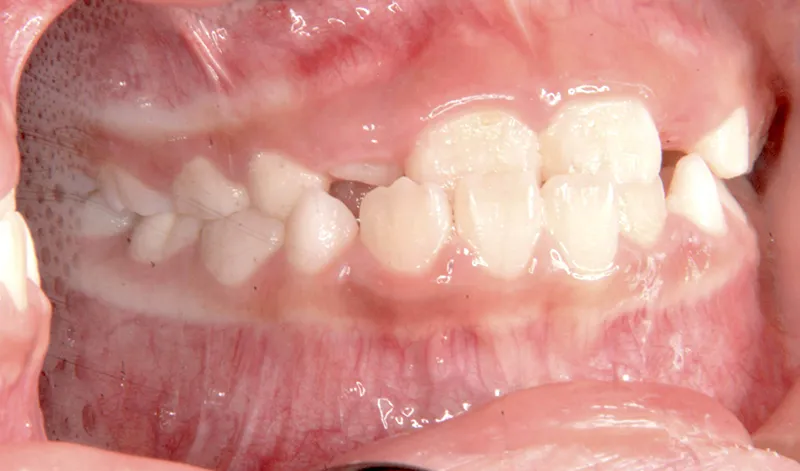

| 初診時年齢 | 小学校1年生(女性) | 主訴 | 受け口 | ||

| 診断名 | 叢生・反対咬合 | 装置名 | 拡大床 | ||

| 抜歯の有無 | 非抜歯 | 治療期間・通院回数 | 2年7ヶ月・21回 | ||

| 費用 | 481,890円(税込) | 費用内訳 | 相談料:1,050円 検査料:46,200円 施術料:210, 000円 装置料:105,000円 保定装置料:52,500円 調整料:3,150円×10回=31,500円 以上 消費税率5% / 調整料:3,240円×11回=35,640円 以上 消費税率8% | ブラケット・ ワイヤー |

付けずに治した |

| 特徴 |

固い食べ物が嫌い 乳歯列が綺麗に並んでいる ゆがんで生えている よく噛まないで飲み込む |

| 状態 |

永久歯が生える隙間がない(叢生) 受け口(口元が出ている/下顎前突/反対咬合) |

| リスク・副作用 |

矯正歯科治療に伴う一般的なリスク・副作用

|